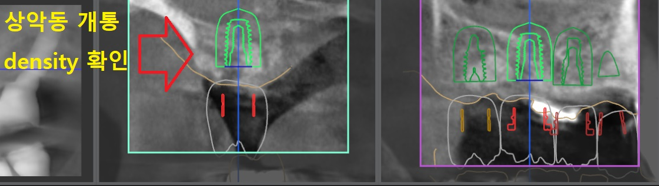

『디지털 임플란트 진단』

우선 이 분은 4개의 어금니 임플란트를

심어드릴 예정입니다.

컴퓨터 진단에서도 4개를 심으면,

좋은 결과를 얻을 수 있다는 것으

알려줬고

4개를 나란히 심으려면,

화면에서 보고 계신 것 처럼

정밀 진단이 반드시 필요합니다.

모내기 하듯이, 나란히 심어야

보철도 잘 연결이 되면서 올바른

교합력을 형성 시킬 수 있기 때문입니다.

옆에서 봐도, 임플란트 4개가

나란히 심겨진 가상 결과를 보여줍니다.

근데 이 분의 경우에는,

시술을 해야 되는 곳 상방에

상악동 이라는 빈 공간이 있습니다.

처음에는 안 해도 될 줄 알았는데,

이렇게 디지털 진단을 하니

상악동 골이식을 하지 않으면,

상악동 천공이 나타난다는 결과를

보여줍니다.

따라서, 뼈 이식 및 상악동 거상술을

같이 병행하기로 했습니다.